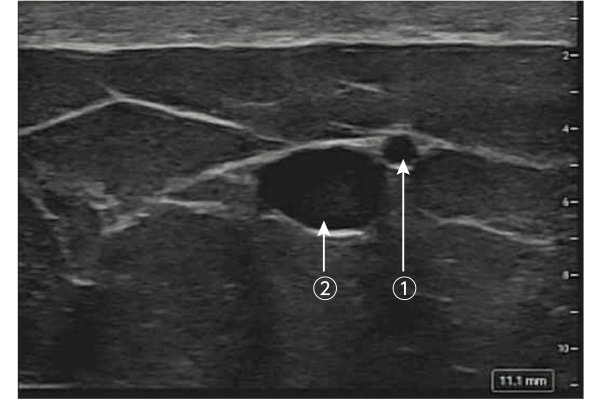

より浅層の動静脈の同定に貢献し、菲薄皮弁の拳上を効率的に支援します。

① SIEA(浅下腹壁動脈)0.9mm(右)

② SIEV(浅下腹壁静脈)2.6mm(左)